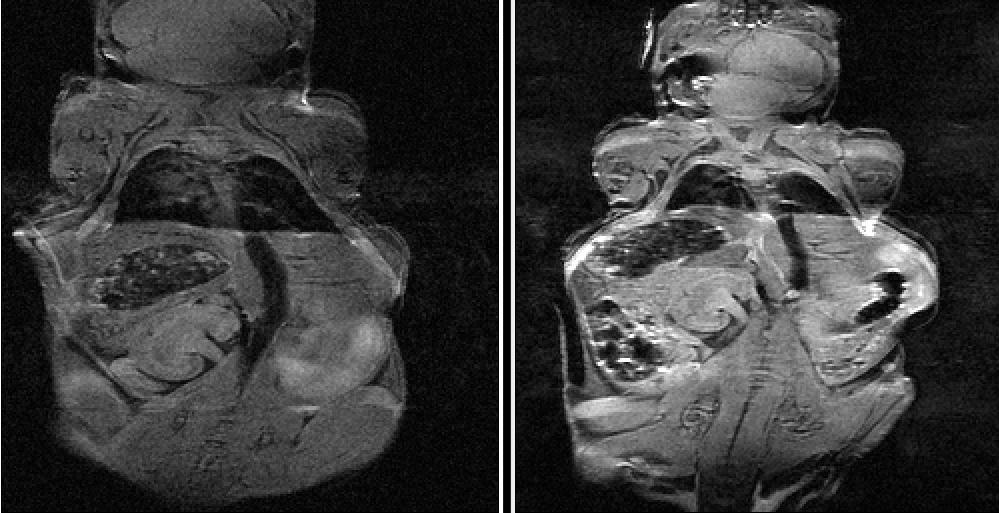

A collaboration with the imaging facility at Fred Hutch Cancer Center has demonstrated that py-me-glucoverdazyl is an effective T1w contrast agent

Preliminary in vivo MRI Studies

Contrast enhancement was observed in the left kidney (with longer retention than the ocglucoverdazyl) and the bladder We also have data that indicates that our compound is absorbed by the pancreas While we observed no noticeable ill-effects on the mouse, we will be examining the vital organs using the Fred Hutch pathology facilities